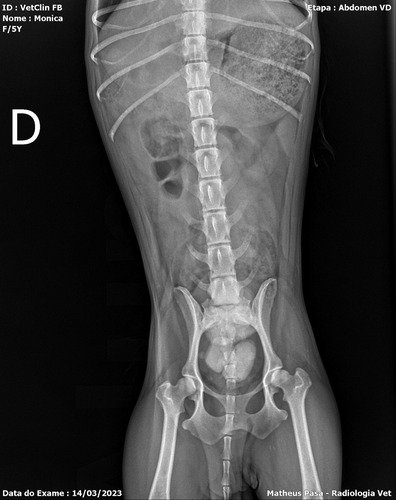

Vamos la, a um mês minha tia resgatou uma cachorrinha linda e amorosa, mas com uma história muito triste, ela veio de um lar onde era espancada todos os dias ( onde qualquer pessoa q fale alto, faça qualquer gesto brusco, ela faz xixi de medo), minha tia acabou nos oferecendo para ficarmos com ela, nossa linda momo, ela foi castrada pela Zoonoses dois dias antes de pegarmos ela.., pensem num amor de animal, como ela faz muito xixi, optamos por colocar fraldinha nela… uma alegria ela… notamos q os olhos dela está voltando a ter brilho… adotou todos da cosa como seus novos país.. mas logo na primeira semana notamos que o xixi dela estava com sangue, levamos ela onde foi castrada e nos disseram q poderia ser q ela foi castrada no período do cio… e até mesmo seria uma limpeza… mas passaram medicamentos, no inicio funcionou o xixi voltou ao normal, mas percebemos que ela tinha dores , e logo voltou o sangue no xixi junto com sangue coagulado.voltamos levar ela para ver o que tem de errado, e acabamos de descobrir que nosso novo bebê tem mais de seis cálculos renais enormes e que a bexiga pode se romper a qualquer momento, Ela está internada e sendo medicada, hoje será a cirurgia dela, mas como o custo de cirurgia, internamento ,medicação e alimentação (que será diferenciada, vai passar dos $3500,00. alguma coisa consegui… mas estás custas maiores não temos condições de arcar… então peço que ajudem esse serzinho qué foi tão violentado (provavelmente era matriz reprodutora) onde só apanhava , que nunca teve amor. as doações podem serem feitas pelo pix 46991109556